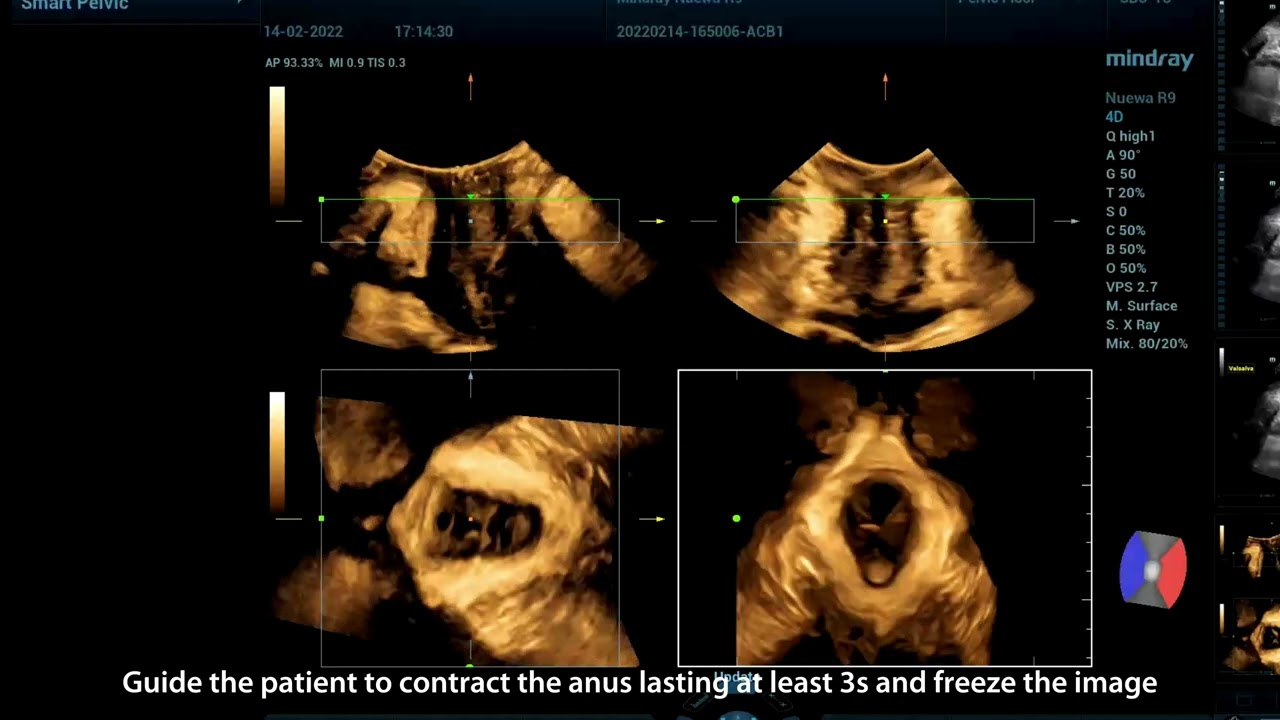

Pelvic ultrasound is considered as the first choice of imaging examination method to evaluate suspected gynecological diseases in women of all ages. Ultrasonography is usually the only necessary imaging examination to diagnose uterine, ovarian and adnexal diseases because of its wide availability, low cost and advantages of no ionizing radiation. With the development of volume ultrasound technology, 3D ultrasound has become a routine gynecological examination item. Through the acquisition of volume data, 3D ultrasound can display the uterus, cervix, ovary and uterine adnexa on any plane, and has more advantages in evaluating the uterine cavity.

UWN+ CEUS provides excellence contrast agent sensitivity and image penetration to get more diagnosis information for gynecology tumor or other difficult diseases. Also MindrayŌĆÖs STE (Sound Trouch Elastogtaphy) can quantitatively evaluate tissue stiffness which is helpful for previse diagnosis of difficult uterus, cervix and ovary diseases.